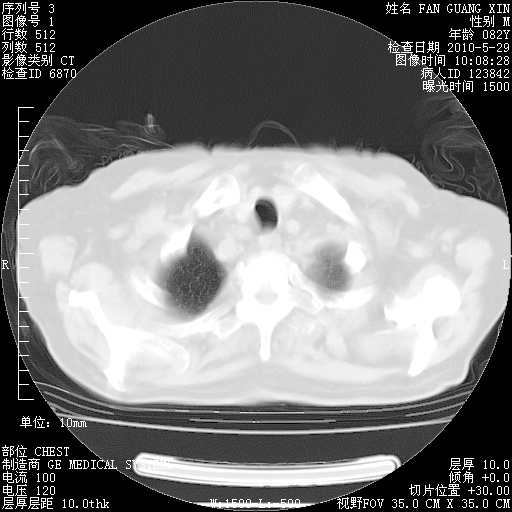

再治疗10天后的肺部CT

阅读此次胸部CT,肺间质渗出性改变较入院时有吸收。目前从体温、白细胞、中性分叶明显增高,肯定存在细菌感染(发生医院感染哦,若无消化道及泌尿系统等感染的依据,肺部感染可能大)。若你院头孢哌酮舒巴坦钠耐药率较高,同意你的方案,若48小时体温仍高,可考虑使用碳青霉稀类抗菌药物,同时可予超声雾化、注意滴数时加大液体量。白蛋白33.30g/L较低哦,需加强营养等支持治疗。